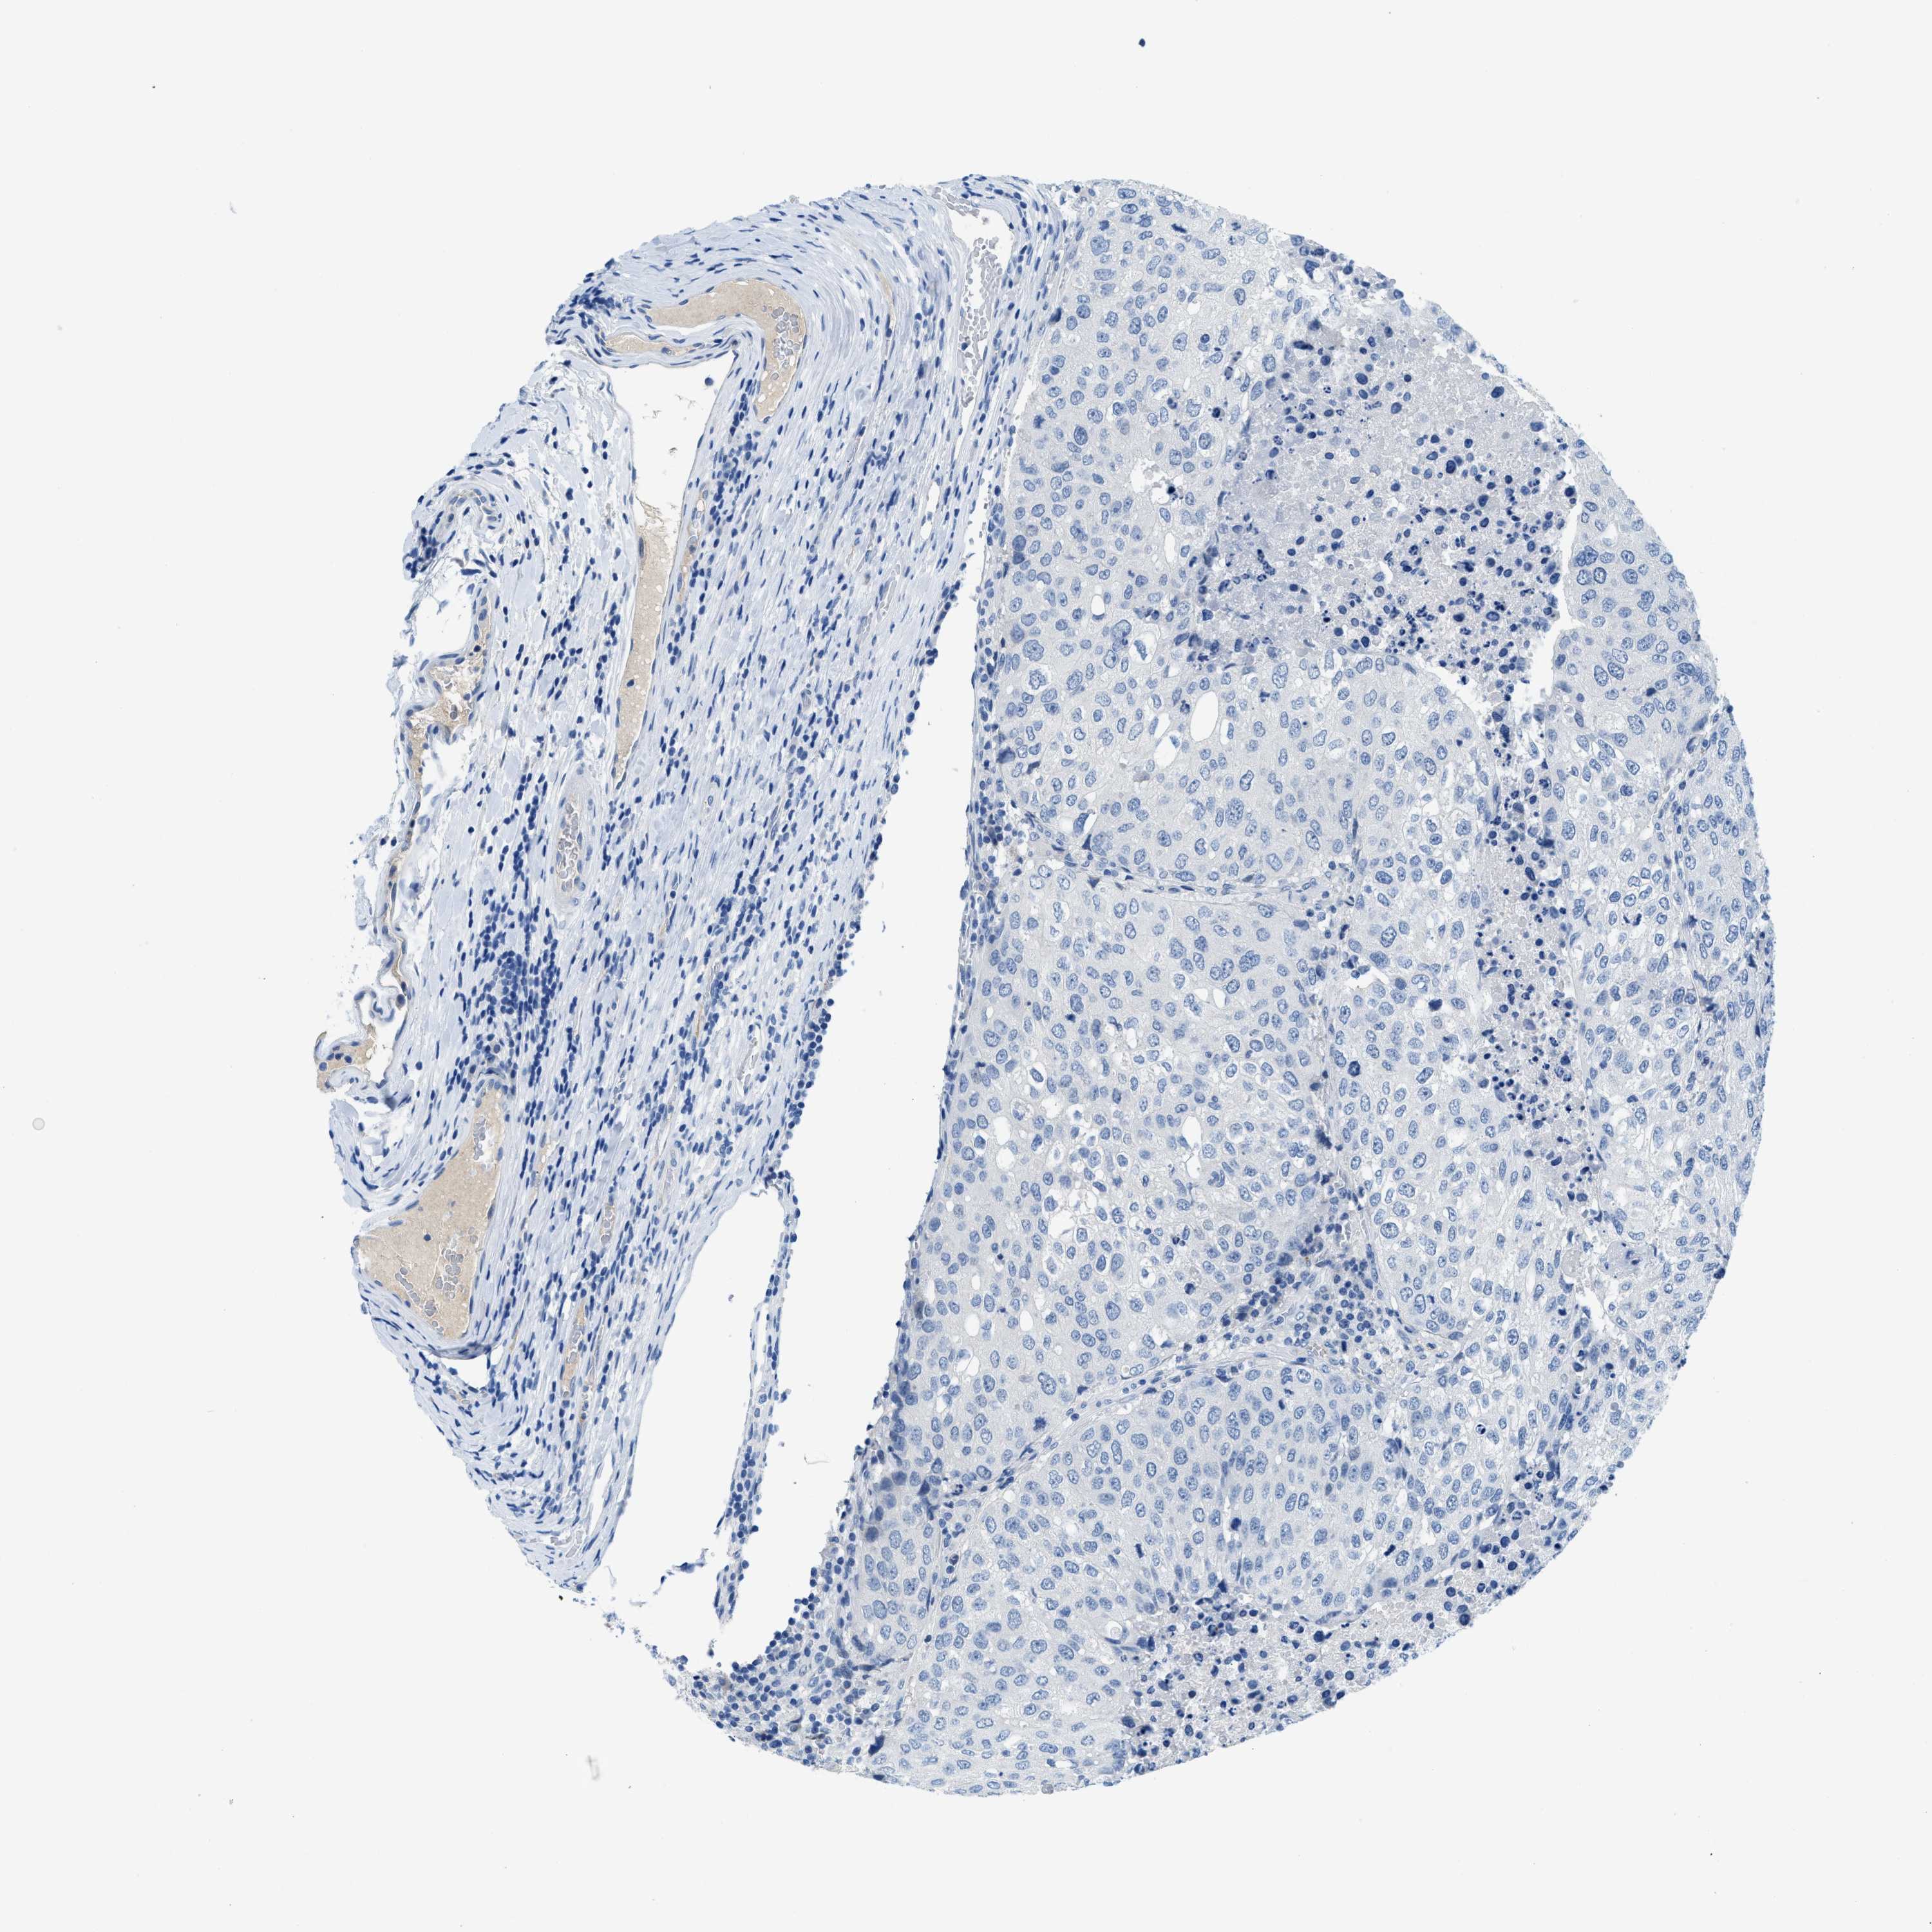

UROTHELIAL CANCER - Protein expressioni

A mouse-over function shows sample information and annotation data. Click on an image to view it in a full screen mode. Samples can be filtered based on level of antibody staining by selecting one or several of the following categories: high, medium, low and not detected. The assay and annotation is described here.

Antibody stainingi

Antibody staining in the annotated cell types in the current human tissue is reported as not detected, low, medium, or high, based on conventional immunohistochemistry profiling in selected tissues. This score is based on the combination of the staining intensity and fraction of stained cells.

Each image is clickable and will lead to virtual microscopy that enables deeper exploration of all samples and also displays staining intensity scores, fraction scores and subcellular localization as well as patient and tissue information for each sample.

Antibody HPA002027

Antibody CAB016782

Staining

High

Medium

Low

Not detected

Intensity

Strong

Moderate

Weak

Negative

Quantity

>75%

75%-25%

<25%

None

Location

Nuclear

Cytoplasmic/membranous

Cytoplasmic/membranous,nuclear

Urothelial carcinoma, High grade

Urothelial carcinoma, Low grade

Adenocarcinoma, NOS